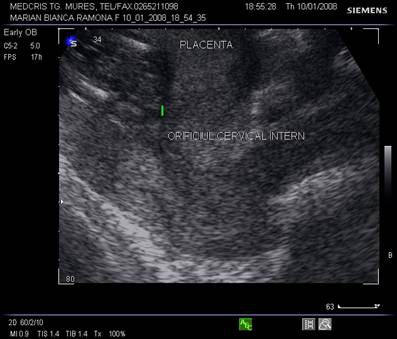

Fig. nr.206. Placenta normal inserata pe peretele anterior uterin , cu marginea sa inferioara la 4 cm de orificiul cervical interin

Diagnosticul ecografic se face urmarind marginea placentara inferioara si raportul cu orificiul cervical intern. O imagine mai buna necesita vezica urinara in semipletie sau chiar o ecografie transvaginala.

Fig. nr.217. Placenta praevia centrala la 15 saptamani ( linia indica raportul placenta praevia cu orificiul cervical intern)